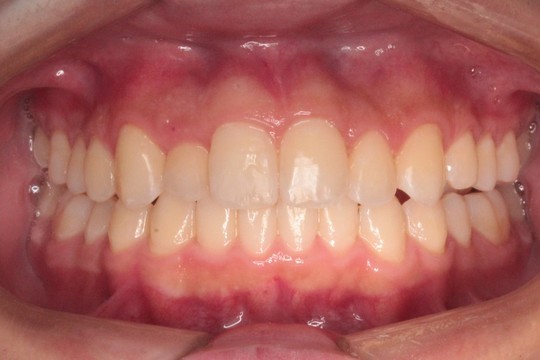

治療後

交叉咬合と重度叢生を非抜歯のインビザラインで治療しました

調布市の20代男性

主訴:歯並びをきれいにしたい

使用装置:インビザライン

治療期間:約3年

治療費用:93.5万円(税込)

治療結果:交叉咬合と叢生が改善されました